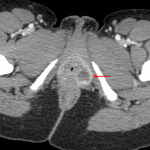

Indication: Lower abdominal pain

- 3.3 cm left ovarian cyst with adjacent high density material

- 2.3 cm peripherally enhancing fluid-density structure along the left vaginal introitus with surrounding fat stranding

- Small volume intermediate density fluid layering in the anatomic pelvis

- Ruptured ovarian cyst

- Infected Bartholin gland cyst

Findings suggestive of ruptured left ovarian cyst with associated small volume hemoperitoneum.

Left Bartholin gland cyst with surrounding inflammation, which could represent superinfection. Recommend correlation with exam.